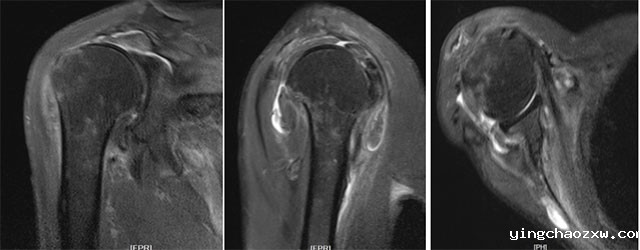

3.术前磁共振检查显示严重的肩袖撕裂。

据悉,该患者为男性,现年85岁,近年来反复感觉右侧肩关节疼痛不适,屡次开展保守治疗,但效果不佳。近半月来疼痛加剧,肩关节活动障碍,严重困扰患者日常生活。患者入院后,陈志强主任医师及其团队认真研讨患者病情,因患者肩袖多年陈旧性断裂已经无法修复,传统全肩关节置换术治疗此类病例肩关节功能根本不能改善和恢复,团队最终决定为患者选择了目前业界治疗此类疾病的最佳治疗方案——反置式肩关节置换术进行治疗。在陈志强主任医师和骨外科全体医务人员的共同努力下,本次手术非常顺利,历时1小时即告完成。术后一周,患者肩关节疼痛消除,功能恢复良好,患者及家属对治疗效果非常满意。